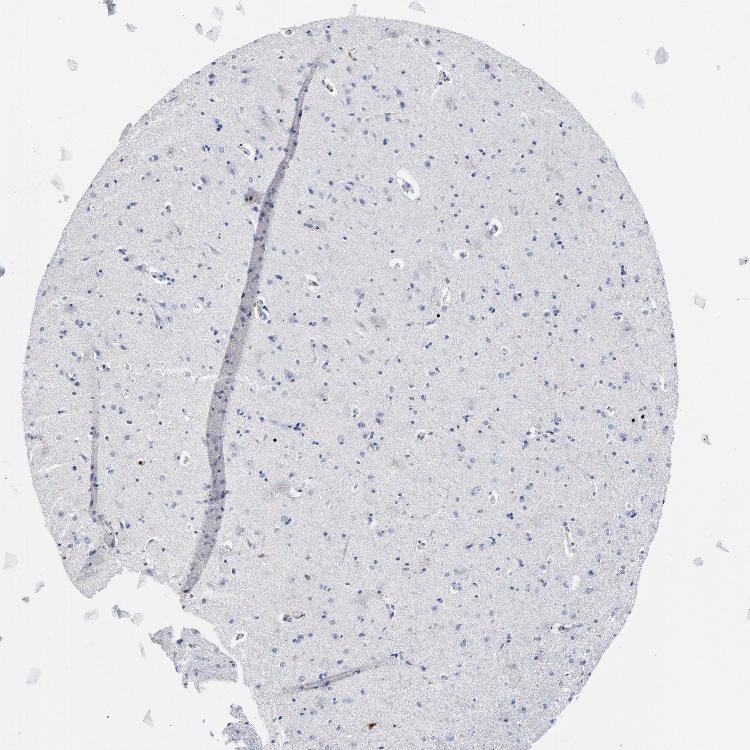

CEREBRAL CORTEX - Antibody stainingi

Antibody staining in the annotated cell types in the current human tissue is reported as not detected, low, medium, or high, based on conventional immunohistochemistry profiling in selected tissues. This score is based on the combination of the staining intensity and fraction of stained cells.

Each image is clickable and will lead to virtual microscopy that enables deeper exploration of all samples and also displays staining intensity scores, fraction scores and subcellular localization as well as patient and tissue information for each sample.

Antibody HPA047836Antibody HPA052095Antibody CAB004524

Endothelial cells Not detectedNot detectedNot detected

Glial cells Not detectedNot detectedNot detected

Neuronal cells Not detectedMediumNot detected

Neuropil Not detectedNot detectedNot detected